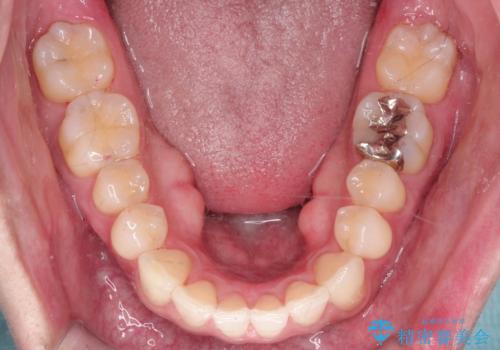

- 前歯の凸凹と顎の偏位を主訴に来院されました。

下顎の偏位を認めましたが、外科矯正を希望されなかったためできる範囲で顎の偏位を治すことができるよう治療を行なっております。

治療開始前に、下顎位の評価をおこなうことで、完成度の高い治療を行うことができました。